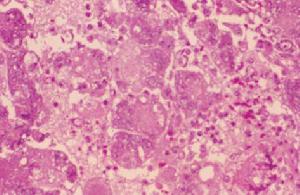

2、全身病變

白喉外毒素進入血液出現全身重度現象,可引起重度性心肌炎,腎炎、周圍神經炎或腦神經損害。